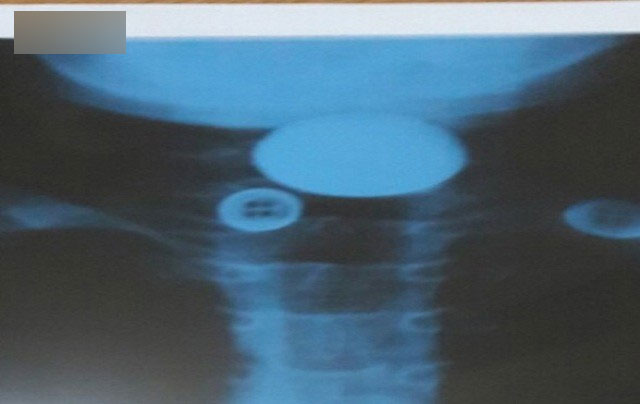

Tại đây, các bác sĩ chỉ định cho bệnh nhi chụp XQuang, hình ảnh cản quang cho thấy dị vật là một hình tròn như đồng xu ngang đốt cổ C5, C6, vị trí ngang giữa cổ. Ngay lập tức bệnh nhi được đưa vào phòng gây mê và tiến hành nội soi gắp dị vật.

BSCKII. Nguyễn Anh Dũng, phụ trách khoa Tai mũi họng (Bệnh viện Hà Đông) cho biết, qua quá trình nội soi phát hiện dị vật là một đồng xu nằm ngang, cách miệng 4-5cm.

"Do dị vật đồng xu khá to nên ống soi dù đã dùng loại to cũng không thể gắp dị vật ra được. Vì thế các chúng tôi phải dùng kẹp gắp kiểu hàm cá sấu, kéo đồng xu vào cửa ống nội soi để rút ra. Sau khi gắp dị vật, kết quả kiểm tra lại niêm mạc thực quản bệnh nhi không phát hiện có tổn thương", BS Dũng cho hay.